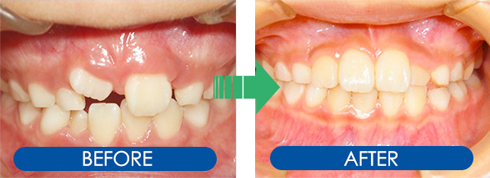

矯正治療のビフォーアフター

頑張って取り組んでいただいた子ども達の症例をご覧ください!

「プレオルソ」による治療法

叢生症例1